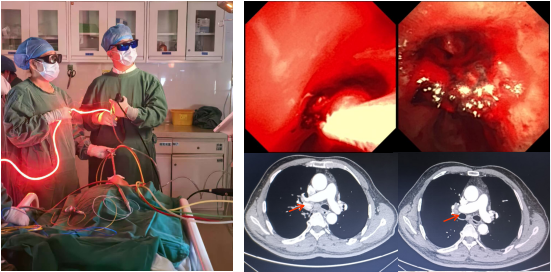

气道肿瘤光动力治疗

图片17.png